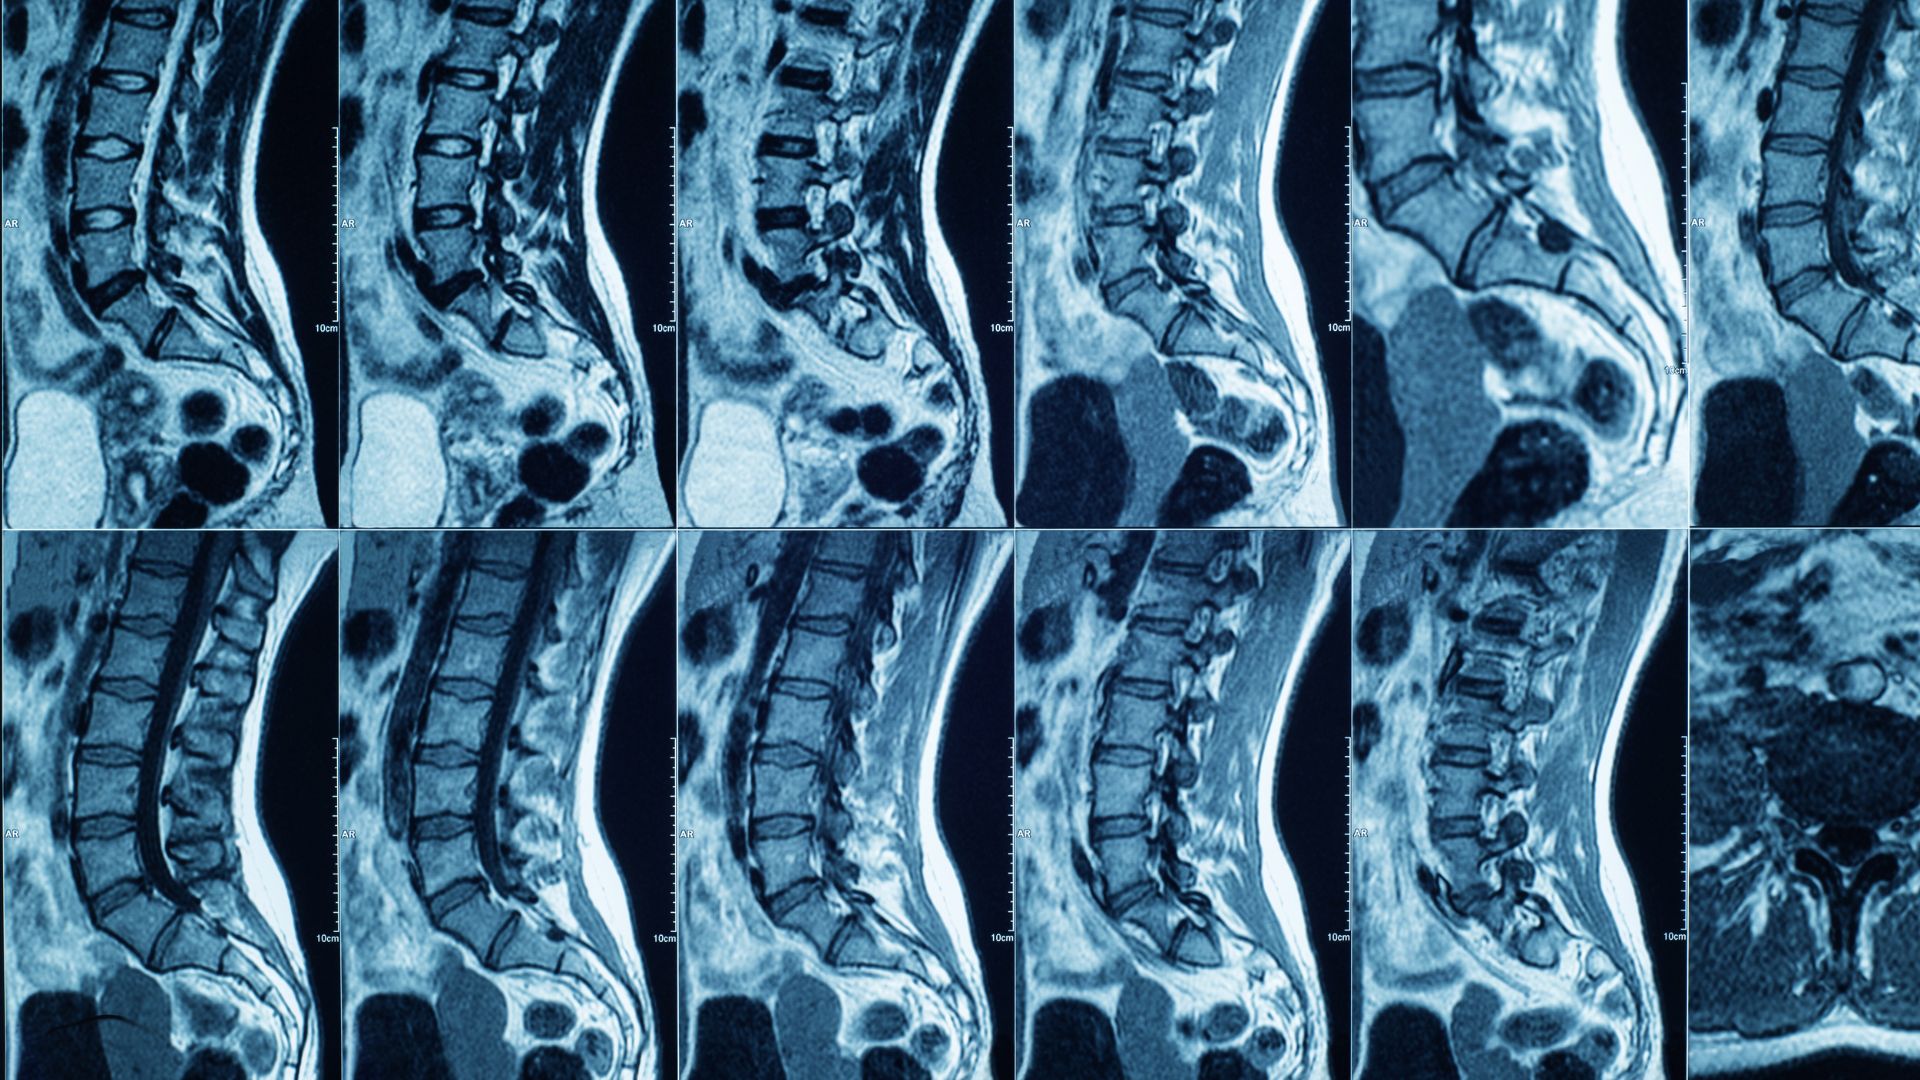

Chụp MRI cột sống là phương pháp sử dụng từ trường mạnh kết hợp sóng radio để tạo ra hình ảnh chi tiết của cột sống và các cấu trúc liên quan. Kỹ thuật này không sử dụng tia X, giúp hạn chế nguy cơ phơi nhiễm bức xạ so với một số phương pháp chẩn đoán hình ảnh khác.

Ưu điểm nổi bật của chụp MRI cột sống là khả năng quan sát rõ mô mềm, đĩa đệm, dây chằng, tủy sống và rễ thần kinh. Nhờ đó, MRI cung cấp thông tin chính xác về mức độ tổn thương, vị trí và bản chất bệnh lý, hỗ trợ bác sĩ đưa ra hướng điều trị phù hợp.

So với X-quang chỉ cho hình ảnh xương và CT scan chủ yếu đánh giá cấu trúc cứng, MRI vượt trội trong phát hiện các bất thường sớm ở mô mềm và thần kinh. Đây là lý do chụp MRI cột sống thường được chỉ định khi người bệnh có triệu chứng kéo dài hoặc nghi ngờ bệnh lý phức tạp.

Ngoài ra, với độ phân giải cao, chụp MRI cột sống có thể phát hiện nhiều bệnh lý khác nhau. Phổ biến nhất là thoát vị đĩa đệm, tình trạng nhân đĩa đệm chèn ép rễ thần kinh gây đau lan, tê bì hoặc yếu cơ. Hơn nữa, MRI còn giúp chẩn đoán thoái hóa cột sống, hẹp ống sống, viêm cột sống, u tủy, chèn ép tủy sống, tổn thương dây chằng và các bất thường bẩm sinh.